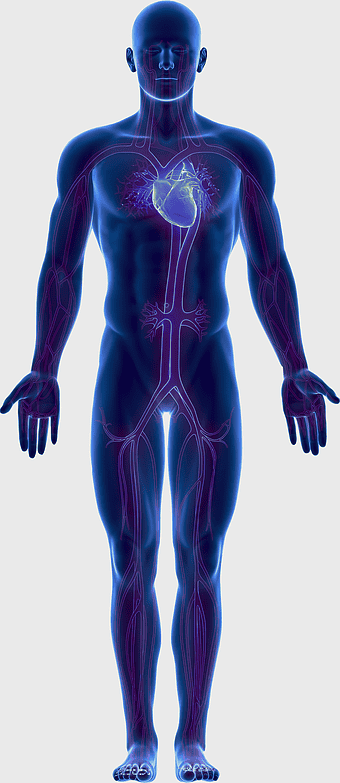

human circulatory system, blood vessel anatomy, weight loss exercise benefits, heart and artery health, vascular network visualization, cardiovascular health illustration, systemic circulation diagram -

blue human anatomy illustration, human circulatory system diagram, digital human skeleton image, electric blue medical figure, human nervous system visualization, human body organ map, human health care graphic -